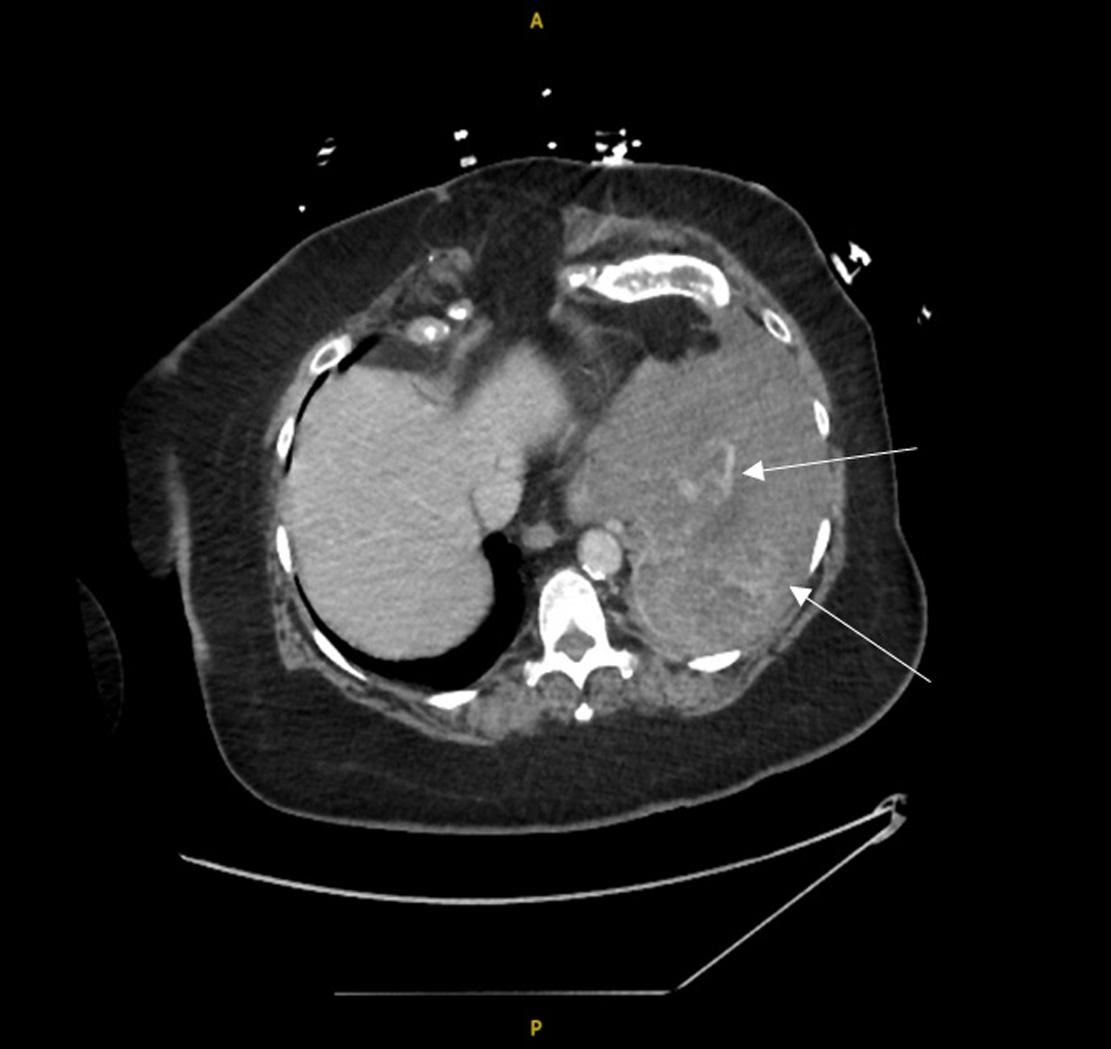

Emergentcomputedtomographyoftheabdomenand pelvisrevealedalargeleftretroperitonealandperitoneal hematomasecondarytoleftRAArupture,aswellasconcern fordevelopingsplenicinfarctsintheleftlowerrenalpole (Image).Thepatientwastakenemergentlytotheoperating room(OR)forexploratorylaparotomywithintwohoursof EDarrival.Sheunderwentsuprarenalcross-clampingwith repairoftheleftrenalarteryandligationofrenalvessels.She returnedtotheORtwodayslaterforleftnephrectomyand abdominalclosure.Shewasextubatedandtransferredtothe floor.Shewasdischargedhometwodayslaterin goodcondition.